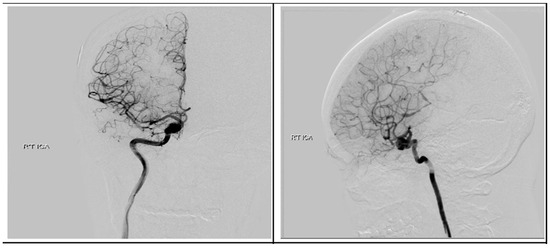

Following discharge, she underwent concurrent chemoradiotherapy with a total dose of 6900 cGy given in 30 fractions in conjunction with temozolomide (TMZ) at 75 mg/m2 daily. Upon a follow-up visitation 6 months post-operation, apart from previous neurologic deficits, she remained in good condition. Surveillance imaging showed no disease progression in the past 18 months after the surgery. We performed digital subtraction angiography (DSA) 4 months later and found no evidence of AVM, but the ICA aneurysm revealed only a sparse change in size without a sign of rupture Figure 9. After a detailed discussion with the patient and her family members, they decided to treat the aneurysm with endovascular intervention.

Figure 9.

Postoperative digital subtraction angiography. Angiography revealed a right supraclinoid internal carotid artery aneurysm.

Regarding the present case, we expected that the supra-clinoid aneurysm would reduce in size after removal of the ipsilateral AVM and glioblastoma due to intracranial hemodynamic changes and fewer angiogenesis-stimulation factors such as VEGF from the tumor. A similar hypothesis was addressed in the current literature and demonstrated good outcomes in cases where intracranial aneurysms and brain tumors simultaneously coexisted [13,14], but unfortunately the postoperative DSA revealed only sparse change in the right ICA aneurysm in the present case. Therefore, the patient still needed to receive intervention involving flow diverter stent placement.